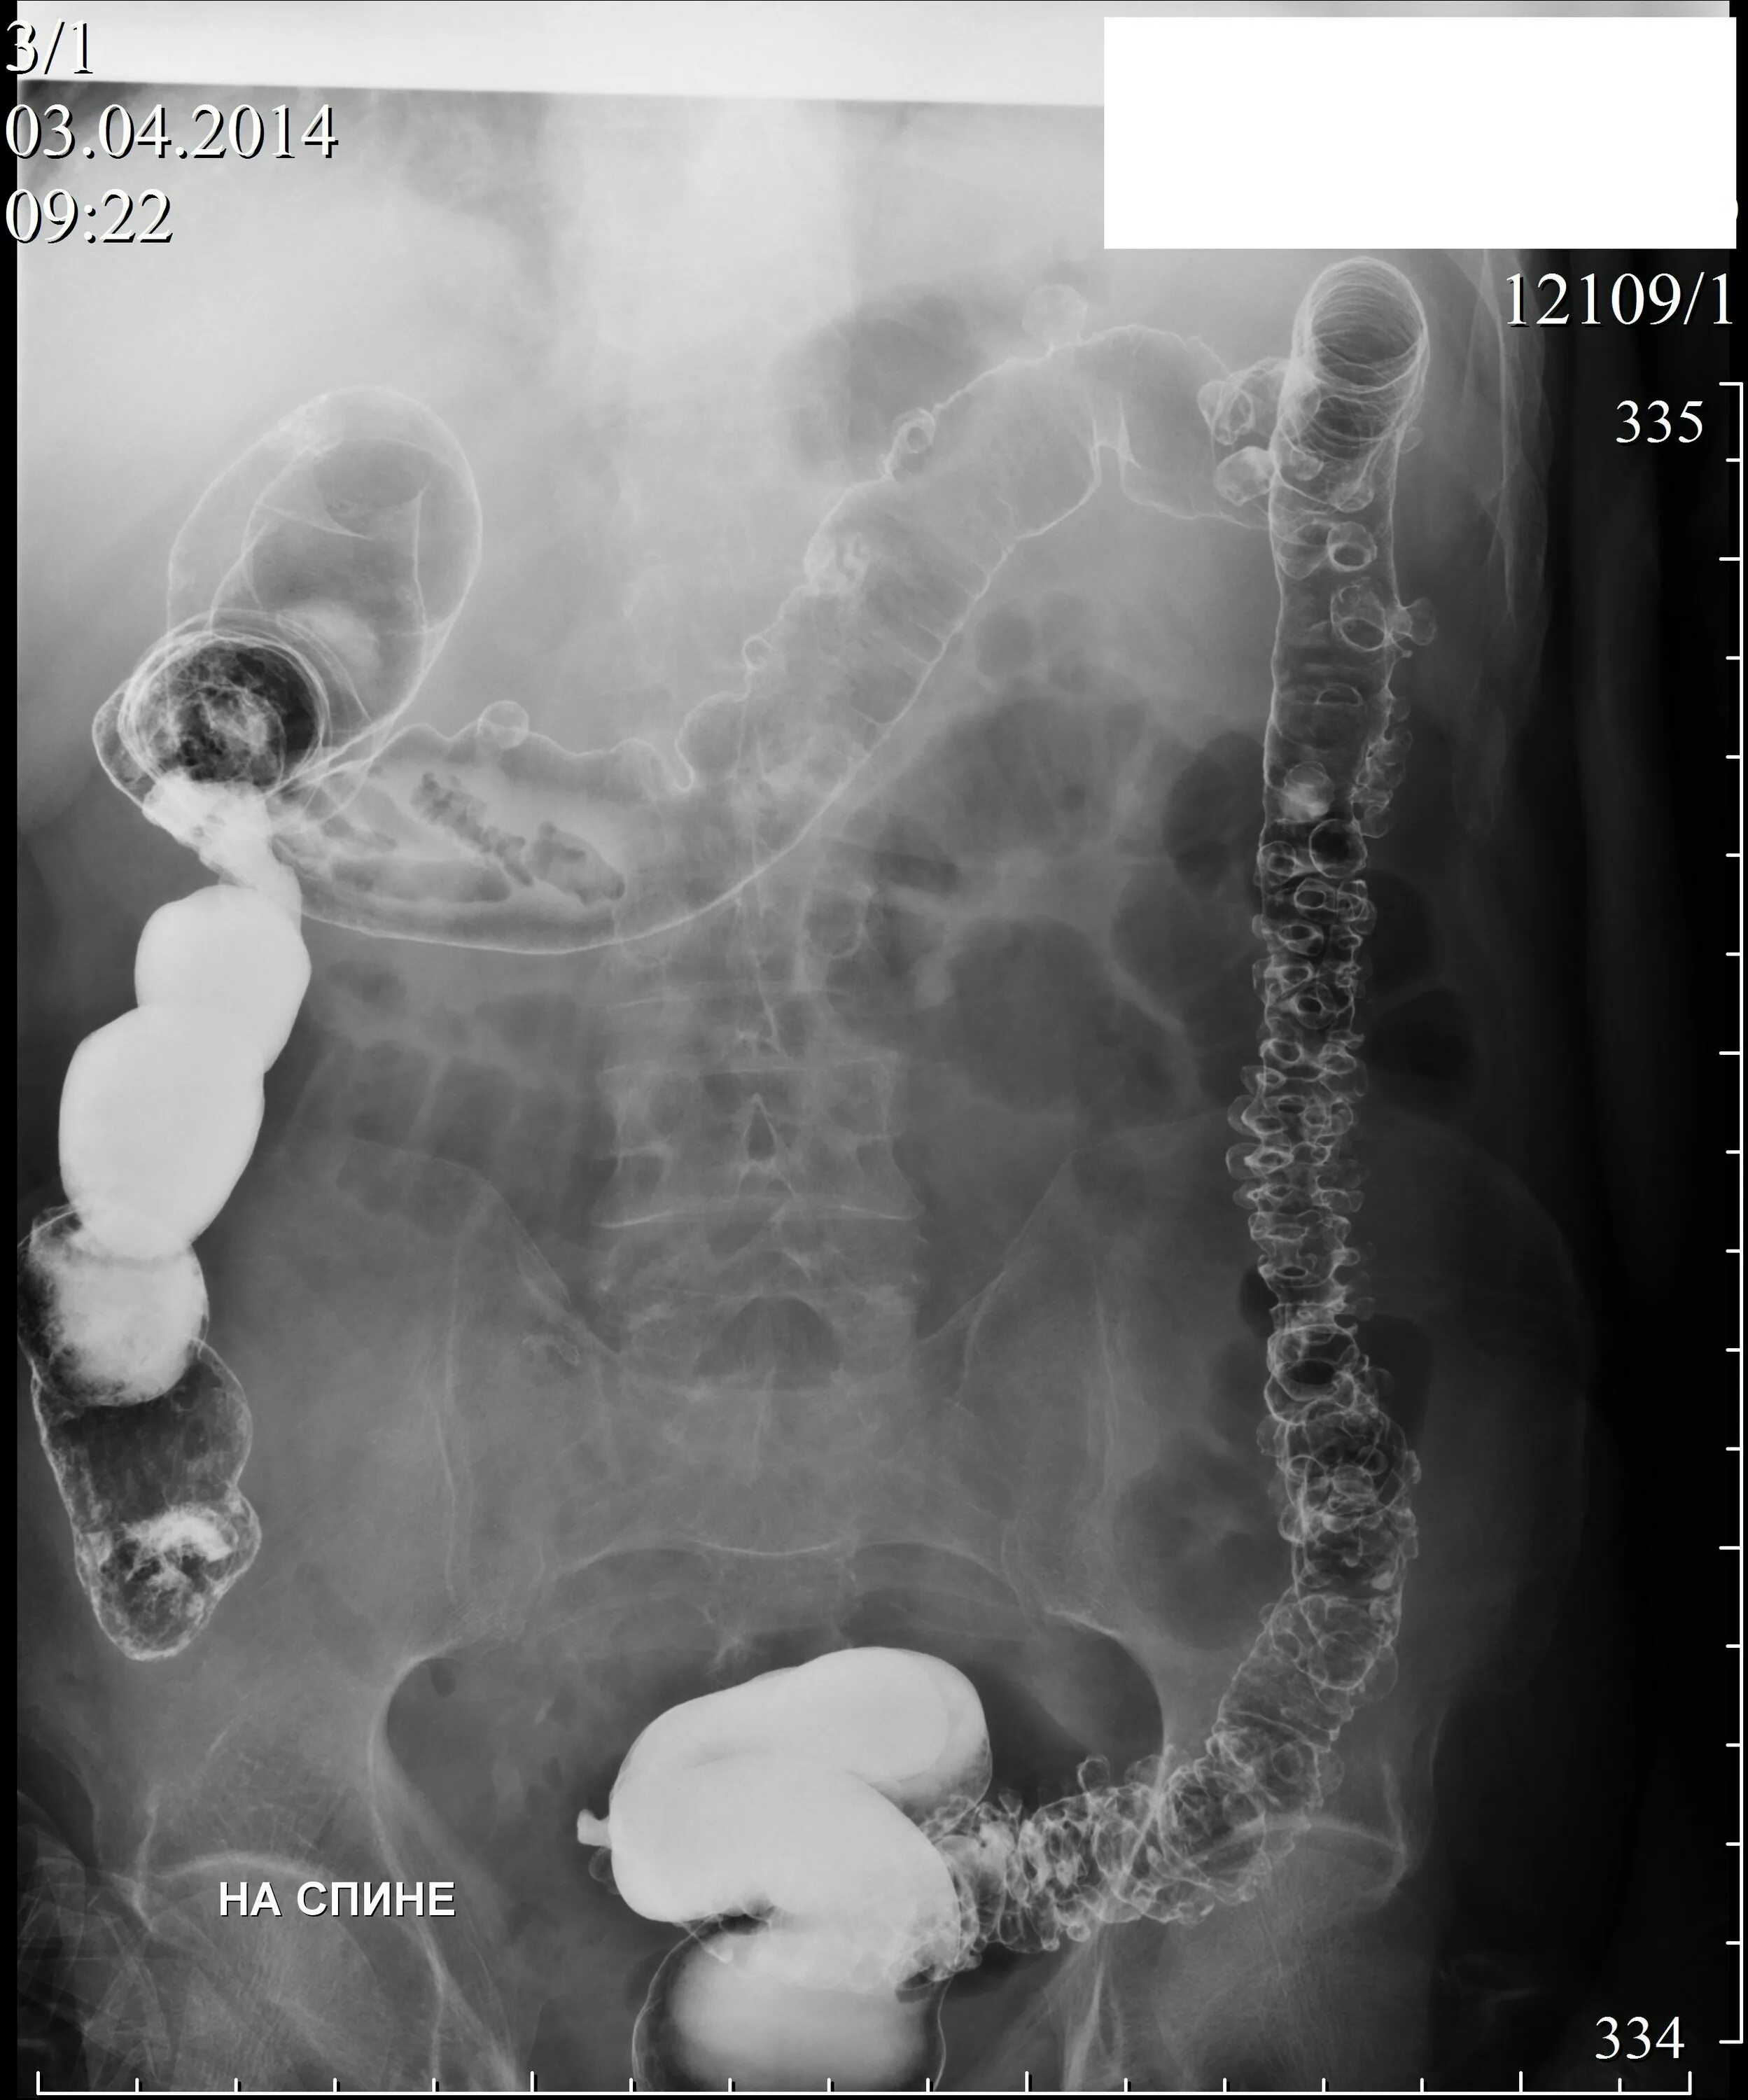

Кишечник после ирригоскопии